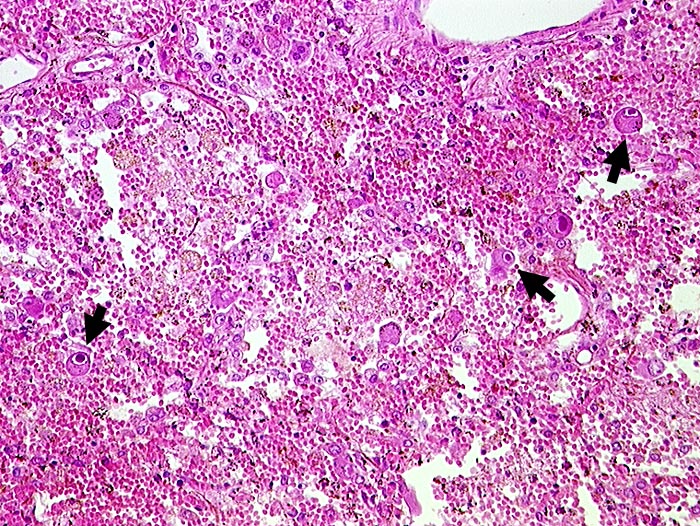

PathoPic – image database / PathoPic ID 216 - CMV (Zytomegalie) Pneumonie

CMV (Zytomegalie) Pneumonie

Virale Kerneinschlüsse mit Halo in Pneumozyten (sogenannte Eulenaugenzellen). Intraalveoläre Hämorrhagie.

HIV positiv seit 5 Jahren. Nachweis von zytomegalen Zellen im Hirn, in der Lunge, im Gastrointestinaltrakt, den Nieren und der Nebenniere. Zusätzlich bakterielle Pneumonie.